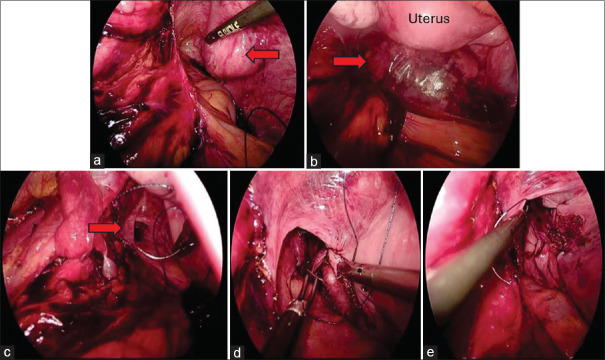

Introduction: Natural orifice specimen extraction surgery (NOSES), particularly transvaginal NOSES, is an innovative approach in laparoscopic urological surgery. This study aims to assess the feasibility, safety, and outcomes of transvaginal NOSES in women undergoing laparoscopic simple nephrectomy in an Indian cohort.

Methods: A prospective observational study was conducted from September 2022 to May 2024 in the department of urology, including 15 women with prior vaginal deliveries undergoing simple nephrectomy. Exclusion criteria were vaginal scarring, previous pelvic surgeries, active intravaginal infections, cervical neoplasia, unresolved pelvic inflammation, and patient refusal. Parameters assessed included operative time, specimen extraction time, blood loss, postoperative recovery metrics, Female Sexual Function Index, and Pelvic Floor Impact Questionnaire scores at the baseline and at 3 months.

Results: The mean age of the patients was 45.73 years. The average operative time, including the specimen extraction was 127.8 min and the average extraction time was 30.13 min. None required conversion to open surgery, and the average blood loss was 68.0 mL with no intraoperative transfusions. The postoperative recovery was rapid, with milestones achieved within 1 day, and the average hospital stay was 2.2 days. Pain scores were low (Visual Analog Scale: 2.87 at 24 h and 1.47 at 48 h). The complication rate was 6.67%, with one case of vaginal bleeding which was managed conservatively. Postoperative pelvic floor and sexual functions were preserved without significant adverse effects.

Conclusion: Transvaginal NOSES is a feasible and safe technique for nephrectomy, offering reduced postoperative pain, minimal blood loss, and rapid recovery, enhancing surgical outcomes and patient satisfaction.